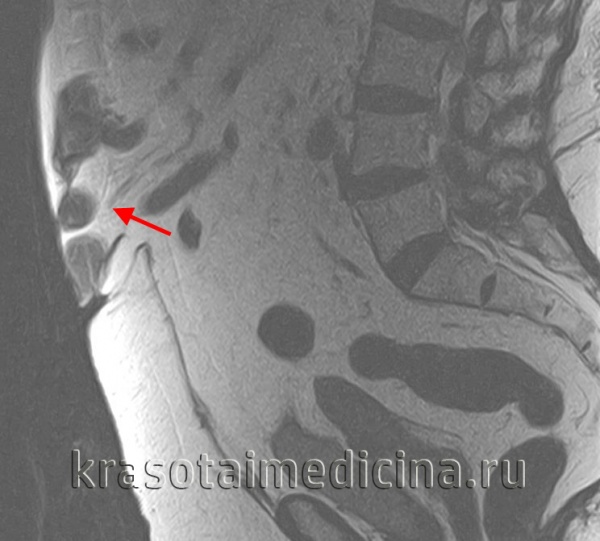

Для уточнения анатомических структур, вовлеченных в грыжевой процесс, проводится рентгенография желудка с барием, гастроскопия (эзофагогастродуоденоскопия), УЗИ грыжевого выпячивания, МСКТ органов брюшной полости. В ряде случаев выполняется герниография - рентеноконтрастное исследование грыжи. Дифференциальная диагностика осуществляется с язвенной болезнью желудка и двенадцатиперстной кишки, панкреатитом, холециститом.

МРТ ОБП и забрюшинного пространства. Грыжа белой линии живота выше пупка (сальник, брыжейка, часть тонкой кишки)